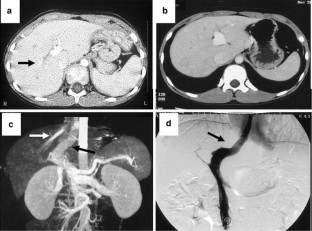

Patent ductus venosus (PDV) is a rare condition, which usually presents secondary to hepatic atrophy and hepatic failure. We have treated eight cases of PDV, all with hypergalactosemia and hyperbilirubinemia. Ultrasonography and three-dimensional computed tomography demonstrated communication between the portal vein and the inferior vena cava. Of the eight PDV cases, three from the older age group (ages 9, 11, and 14 years) had high-density lesions in their brain nucleus, and one case (age 19 years) had undergone prior Kasai portoenterostomy for biliary atresia. Six PDV patients underwent ligation of PDV and the remaining two cases underwent partial banding of PDV with intraoperative monitoring to maintain portal vein pressure (PVP) under 30 cm H2O. Improvement of the intrahepatic portal vein flow was achieved by ligation or banding of PDV. Postoperatively, serum galactose and bilirubin fell to normal ranges, but portal thrombus occurred postoperatively in the first case. We subsequently administered postoperative anticoagulation in the remaining cases and experienced no major complications. These results suggest that PDV ligation and banding are effective surgical approaches for patients with PDV. Close postoperative monitoring to avoid portal thrombus is imperative in these cases.

Fig. 2